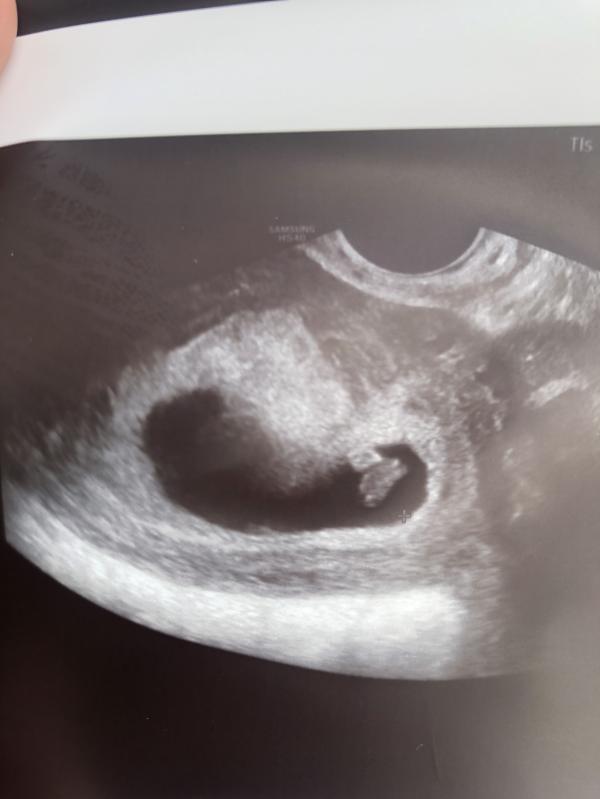

узи в 7недель+4дня

Плодное яйцо -28мм

желточный мешок-4мм

КТР-10мм

сердцебиение 120-130 ударов в минуту

вот и плодное яйцо ,она сказала оно такое из-за перегородки((( самое главное чтобы эта перегородка не помешала в будущем🙏